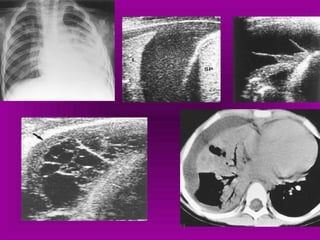

Notice the increased lucency of the cardiophrenic sulci in this patient

with inferior anteromedial pneumothoraces. A CT scan confirms the

diagnosis

 a hyperlucent upper

quadrant with

visualization of the

superior surface of the

diaphragm and

inferiorvena cava.

 double-diaphragm

sign

 Antero lateral air may

increase the

radiolucency at the

costo phrenicsulcus.

This is called the deep

sulcus sign.